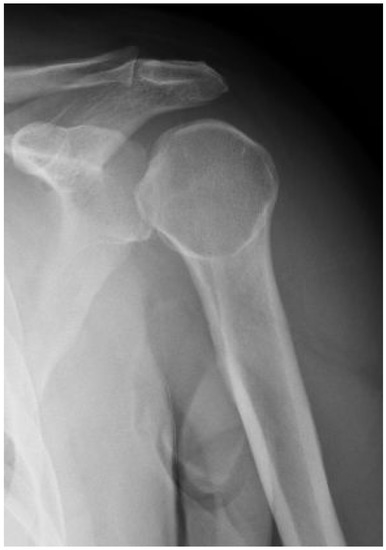

Surgical and Rehabilitative Treatment of Misdiagnosed Posterior Dislocation of the Shoulder: Case Series

| 1 CP | M–49 | 19 days | 22 days | Hill–Sachs reverse lesion <50% | McLaughlin technique Subscapularis tendon transfer |

| 2 DF | F–49 | 70 days | 106 days | Hill–Sachs reverse lesion <50% | Subscapularis tendon transfer |

| 3 AA | M–54 | 6 days | 14 days | Hill–Sachs reverse lesion <50%, humeral insertional detachment of ST and LHB | Subscapularis tendon transfer |

| 4 CI | M–34 | 2 days | 9 days | Hill–Sachs reverse lesion <50% | Repair through a plication of subscapularis tendon (McLaughlin modified technique) |